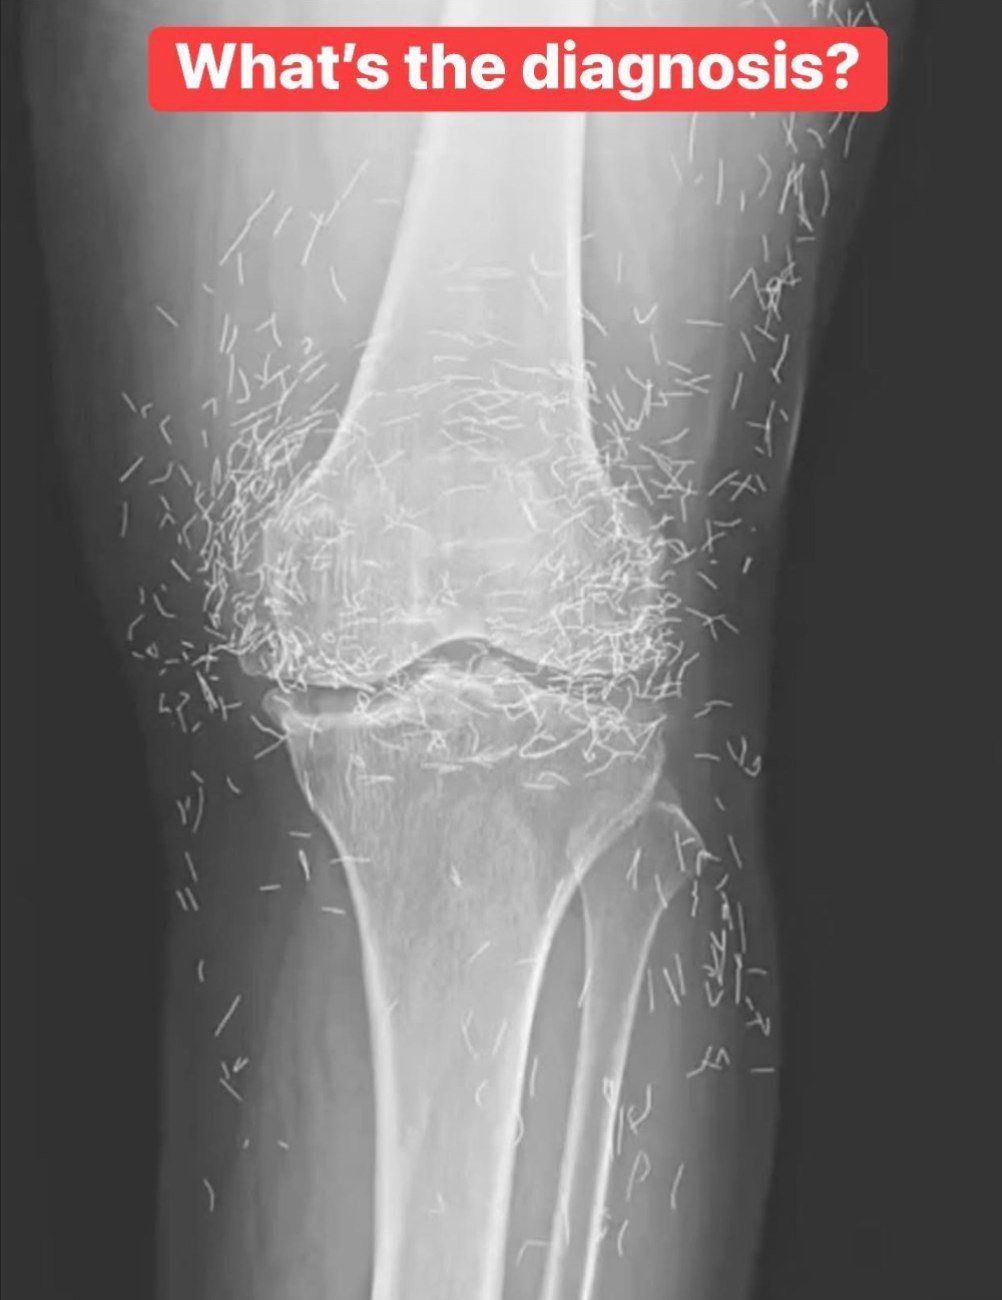

Evidence that acupuncture actually treats medical conditions is limited. Yet it remains a popular option for painful joints, especially in some Asian countries where inserting tiny pieces of sterile gold thread around a joint is a common arthritis treatment.

For this woman, her gold-laden knees are a stark reminder that sometimes, alternative medicine can leave more than just a mark — it can leave a literal treasure trove.